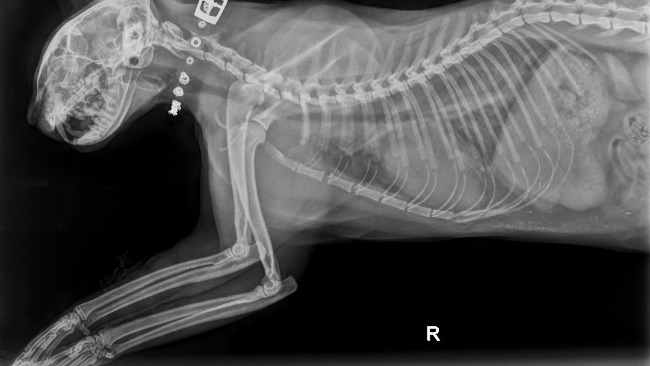

Wykonaliśmy również RTG w 4 projekcjach. Na pierwszy rzut oka wszystko wygląda dobrze, ale czekamy jeszcze na dokładny opis od specjalisty. Dodatkowo kupiłam Kokosowi leki odrobaczające na 3 miesiące, ponieważ jedną z możliwych przyczyn problemów mogą być pasożyty w płucach.

Poniżej dołączam zdjęcia RTG oraz potwierdzenia płatności.

Dostaliśmy opis od specjalisty. Kokos ma powiększone obie zastawki serca oraz wyciek w zatokach ( stąd ten świst u niego ). Będziemy podawać mu antybiotyk w zastrzykach i konieczna jest wizyta u kardiologa (ma odbyć się w przyszły wtorek) . Niestety to wszystko generuję kolejne koszty plus leki na serce które zapewne dostanie po wizycie u kardiologa. Z tego względu wciąż proszę o wpłaty i z całego serca dziękuję!